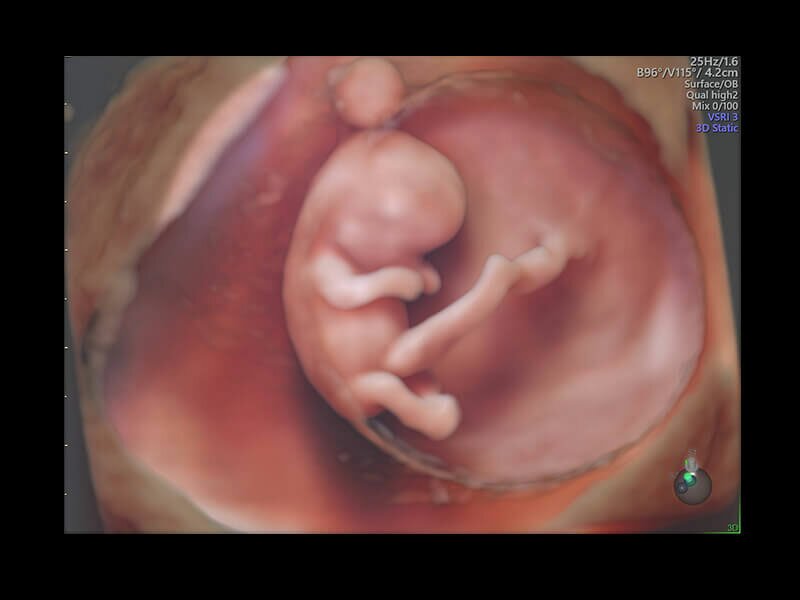

Объемное УЗИ на Voluson E10 — это не просто потрясающе красивая картинка, это ценный инструмент получения дополнительной информации при обследовании женщин.

Voluson E10 поддерживает инновационные технологии формирования изображений — HDlive Silhouette и HDlive Flow, которые позволяют увидеть мельчайшие детали. Алгоритм SonoRenderlive упрощает рабочий процесс и дает возможность реконструировать изображение поверхностей, определяя область перехода между тканью и жидкостью.

• HDlive

Инновационная технология визуализации HDlive обеспечивает получение реалистических изображений за счет эффекта объемного зрения, повышая достоверность клинической оценки. Теперь режим HDlive дополняют две новые функции:

• Технология HDlive Silhouette — задает разный уровень прозрачности, помогая выявлять контуры внутренних структур и точнее оценивать состояние плода в первом триместре.

• Технология HDlive Flow — повышает реалистичность визуализации сосудистых структур, улучшая восприятие глубины (по сравнению с традиционным цветовым допплером и функцией HD-Flow).